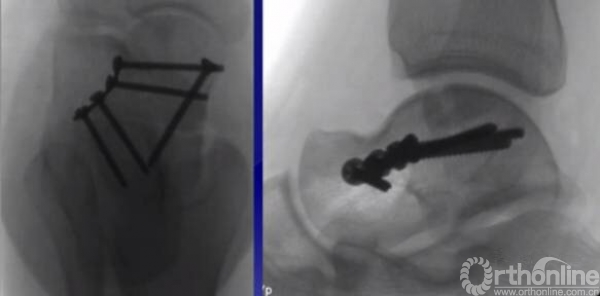

如果一侧钢板的位置不佳,则容易造成另外一侧的骨折裂开。所以最好的固定是一侧用钢板固定,另外一侧可采用螺钉进行加压,对于颈部的骨折,避免另外一侧开口。

2.尽量保护血运,用单侧入路

3.尽量避免关节面内置物